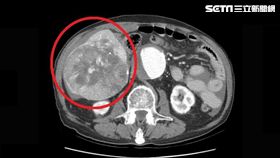

他靠中草藥控制肝癌 腫瘤卻長大奪命

許多民眾一聽到罹患肝癌常不敢面對,因此錯失治療的最佳...

8旬翁草藥治療 肝癌腫瘤破裂身死!

一名罹患肝癌的老翁,因為上了年紀害怕西醫手術治療,竟...